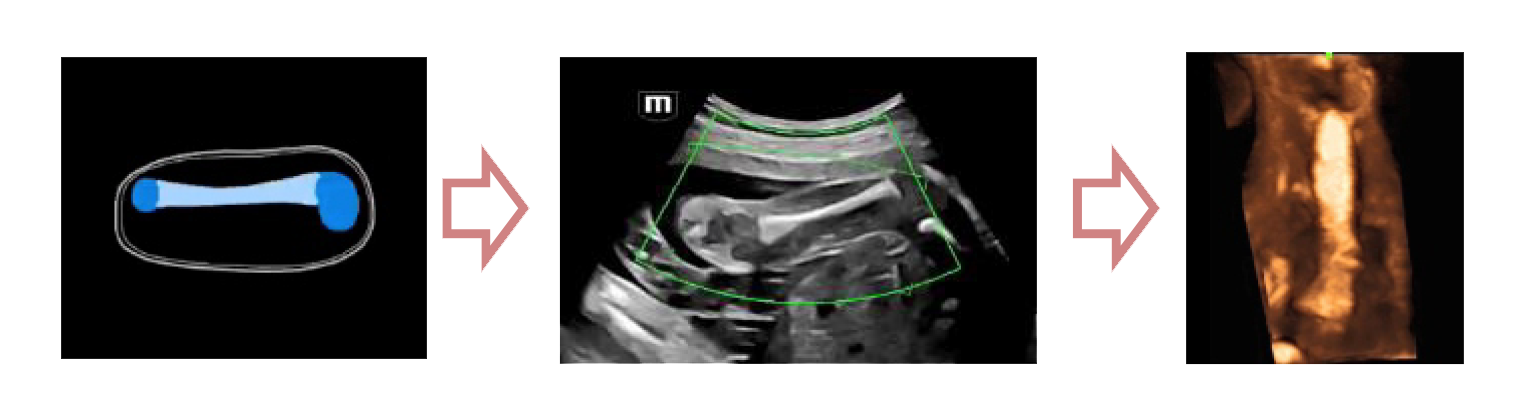

Легкое получение 3D изображения костей

- Автоматическое распознавание костей конечностей плода

- Автоматическая подстройка зоны интереса и положения до оптимального

- Автоматический рендеринг изображения

Место Smart Scene в технологии full-stack smartness